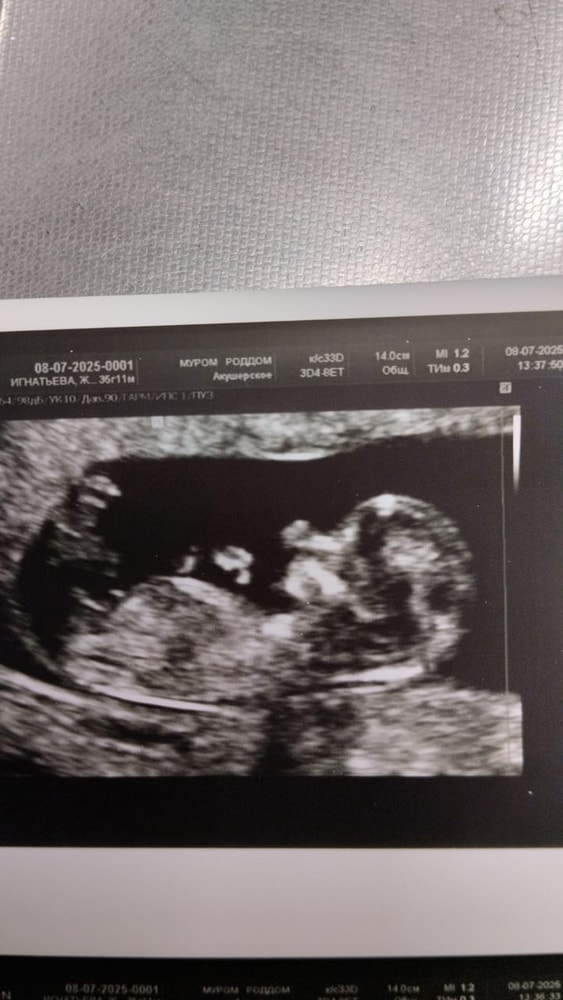

Алена, я так понимаю у автора это с первого скрининга фото узи. По половому бугорку это 100% мальчик, ракурс удачный и точно не девочка

Мышонок, а где вы девочку увидели, там отличный ракурс полового бугорка и это мальчик

похоже на мальчика

Девочка

Мальчик

Сынок☺️

Как говорится закрашиваю кружочек!😁 Пол малыша 🩵🩷